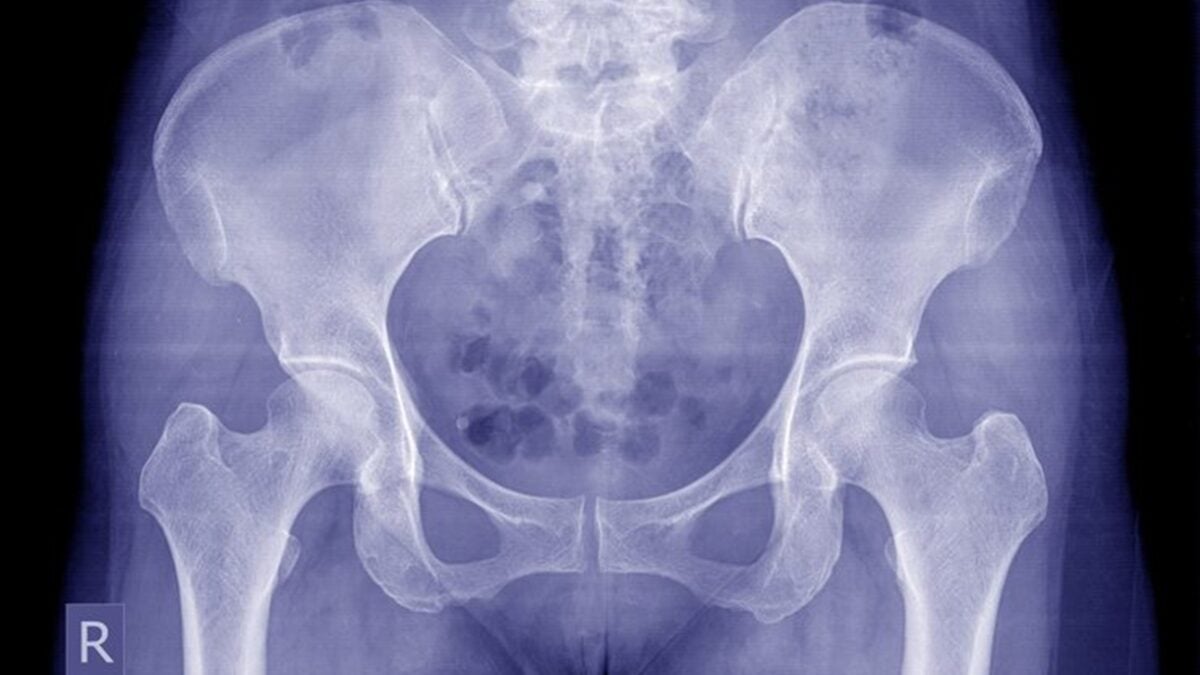

O que Hu não sabia é que o objeto continuou no corpo. A verdade só veio à tona recentemente, quando ela sofreu uma queda de bicicleta e procurou atendimento médico com suspeita de fratura. Uma tomografia 3D revelou o fragmento do termômetro alojado atrás da pélvis.